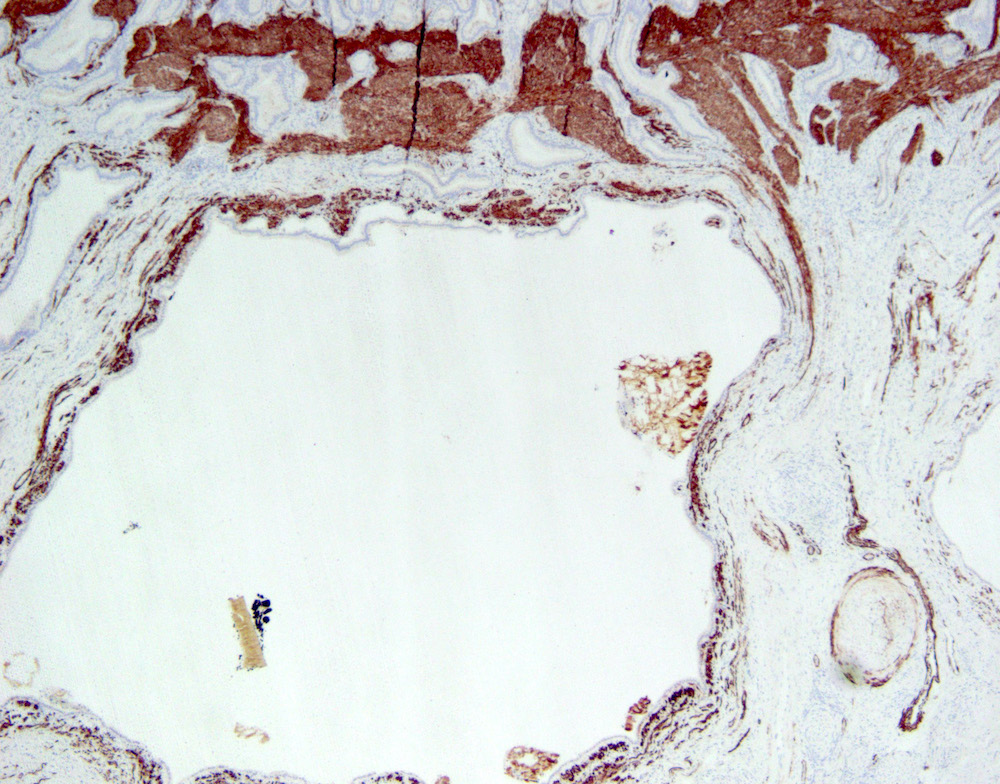

Microscopic (histologic) description

- Cystically dilated benign biliary glands accompanied by smooth muscle hypertrophy of gallbladder wall, thickened / fibrotic subserosa (StatPearls: Adenomyomatosis [Accessed 26 January 2021])

- Glands are distinct from the Rokitansky-Aschoff sinuses, which are epithelial diverticula, usually multifocal and occur throughout gallbladder secondary to injury, versus adenomyomatous nodule (distinct localized lesion of the gallbladder wall, 1 - 1.5 cm mural nodule in the fundus) (Am J Surg Pathol 2020;44:1649)

- May have reactive epithelial changes, papillary change and intestinal metaplasia (StatPearls: Adenomyomatosis [Accessed 26 January 2021])

- Rarely, benign glands are seen in proximity to nerves, appearing as perineural and intraneural invasion only in the subserosal layer (benign gland-like structures may migrate into nerves due to chemotactic factors or signaling substances with activation of cell receptors) (Am J Surg Pathol 2007;31:1598)

- Adenomyomatous nodules may rarely show dysplastic / carcinomatous transformation, whereas dysplasia in Rokitansky-Aschoff sinuses appears to be more common; however, the true association between adenomyomatous nodules and neoplasia has not yet been determined (Am J Surg Pathol 2020;44:1649)

- Recently, papillary dysplastic lesions of adenomyomas have been identified (intracholecystic neoplasms of adenomyomas), demonstrating cystic and solid areas with papillary projections that show biliary, gastric and intestinal phenotypes, with low or high grade dysplasia (Am J Surg Pathol 2020;44:1649)

Microscopic (histologic) images

Contributed by Monica T. Garcia-Buitrago, M.D.